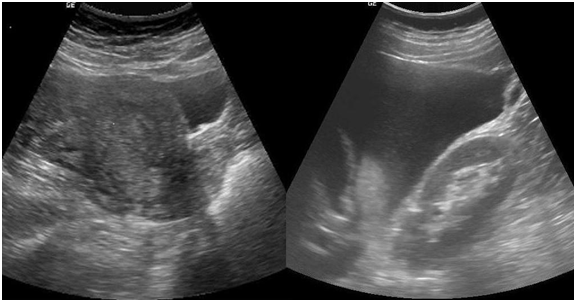

An urgent ultrasonography was done, which reported Single gestational sac with a foetal pole of 9weeks 1day in right adnexal region close to right ovary. Foetal cardiac activity was not present (Figure 1). Uterus was normal in size and echotexture with normal endometrial thickness (Figure 2a). Gross free fluid was noted in peritoneal cavity which on ultrasound guided aspiration came out to be blood suggesting hemoperitoneum (Figure 2b). Ultrasonographic features were consistent with ruptured right adnexal ectopic gestation with possibility of ruptured right ovarian ectopic pregnancy. Her initial blood results were Blood group B positive and Hemoglobin (Hb) 8.7 gm%.

Figure 2 2a-ultrasonography showing uterus with normal endometrial cavity. 2b-ultrasonography showing gross hemoperitoneum.